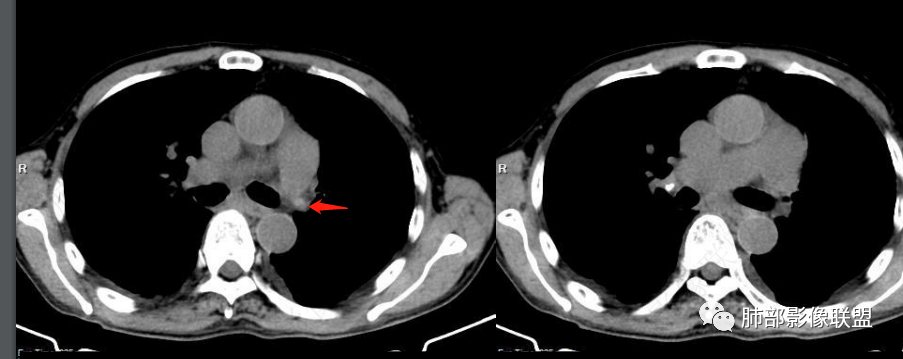

左肺明显肺野透亮度增加,右肺明显肺水肿!右肺血管束稀疏,D二聚体明显高!首选左肺肺栓塞可能

老年女性,胸闷,水肿,气短,bnp高,临床有心功能不全,心彩无左衰依据,胸部ct右肺磨玻璃,小结节,小叶间隔增厚,血管不对称,考虑pe

看一下影像,肺动脉粗大,大于升主动脉

从肺动脉的主体分析:左肺动脉好像起始部就开始狭窄。

现在给的图像:是鼠尾状狭窄,而不会局部膨隆,远端细小那种。

右侧的肺动脉增粗肯定与代偿有关。

现在的问题是自左肺动脉狭窄的原因:是急性栓塞?炎性病变?慢性血栓?

1.老年男性患者,胸闷、双下肢浮肿10余天入院。夜间需高枕入睡。

实验室BNP,D-二聚体升高。肾功能不全。

2.右肺广泛密度增高、腺泡结节样磨玻璃影,血管影明显扩张,小叶间隔增厚。

3.右肺下叶纤维钙化灶。

4.左肺相对广泛低密度、血管纤细(显著)。

5.双侧胸腔少量积液,右侧较为明显。

6.心脏影增大,右房室增大为主。(增强:左心房及肺静脉入口见充盈缺损)

7.肺动脉主干扩张,左侧肺动脉主干见混杂密度影,上下肺动脉似不能连续追踪。

(增强:左肺动脉充盈缺损、闭塞)

8.胸壁见迂曲扩张静脉血管。